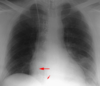

What is the red arrow indicating?

Is this a normal finding on a CXR?

A

• Gastric bubble

• This is a normal finding on a CXR

Free air: Instead of the air being contained inside the stomach to the unitlateral side of the diaphgram, air will be displaced bilaterally on both sides of the diaphragm.